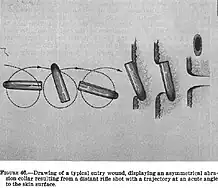

According to the Warren Commission's single-bullet theory—derided as the "magic bullet theory" by conspiracy theorists—Governor Connally was injured by the same bullet that exited Kennedy's neck. The bullet created an oval-shaped entry wound near his right shoulder, struck and destroyed several inches of Connally's right fifth rib, and exited his chest just below his right nipple, puncturing and collapsing his lung. That same bullet then entered his arm just above his right wrist and shattered his right radius bone. The bullet exited just below the wrist at the inner side of his right palm and finally lodged in his left thigh.[73][74][72]

As the limousine passed the grassy knoll,[75] Kennedy was struck a second time, by a fatal shot to the head.[76] The Warren Commission made no finding as to whether this was the second or third bullet fired, and concluded—as did the HSCA—that the second shot to strike Kennedy entered the rear of his head. It then passed in fragments through his skull, creating a large, "roughly ovular" [sic] hole on the rear, right side of the head, and spraying blood and fragments. His brain and blood spatter landed as far as the following Secret Service car and the motorcycle officers.[77][78][79][note 6]

According to the Warren Commission and the HSCA, Kennedy was waving to the crowds on his right when a shot entered his upper back and exited his throat just beneath his larynx.[68][69] He raised his elbows and clenched his fists in front of his face and neck, then leaned forward and leftward. Mrs. Kennedy, facing him, put her arms around him.[65][70][71] Although a serious wound, it likely would have been survivable.[72]